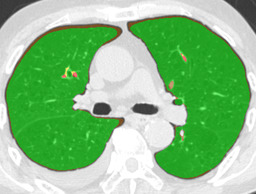

In this paper, we define partial annotation as an annotation format in which only one class is chosen for the annotation and only pixels belonging to the chosen class are annotated per image. For example, in Figure 1(a), although there is ground glass opacity in the image, only consolidation is chosen for annotation and pixels of consolidation are annotated. Partially annotated dataset is less informative for training, however, it is much easier to create compared to fully annotated dataset since annotators only need to focus on one class at a time during the annotation task.

Partially annotated datasets have been utilized previously [8, 9]. In this paper, we propose a new weak supervision technique that fully utilizes partially annotated dataset. Throughout this paper, each DLD pattern is represented or painted in the following colors (CON:cyan, GGO:yellow, HCM:red, EMP:green, NOR:brown.)

Statistics of our dataset are shown in Table 1 and typical images and their annotations for each DLD pattern are shown in Figure 1. In our partially annotated dataset, all the pixels in a slice were manually classified into two classes: dominating DLD pattern and other tissues. In other words, all the pixels in our dataset were assigned one of the labels from either of the two label sets, Lstrong={lCON,lGGO,lHCM,lEMP,lNOR}subscript𝐿𝑠𝑡𝑟𝑜𝑛𝑔subscript𝑙𝐶𝑂𝑁subscript𝑙𝐺𝐺𝑂subscript𝑙𝐻𝐶𝑀subscript𝑙𝐸𝑀𝑃subscript𝑙𝑁𝑂𝑅L_{strong}=\{l_{CON},l_{GGO},l_{HCM},l_{EMP},l_{NOR}\} or Lweak={lCON¯,lGGO¯,lHCM¯,lEMP¯,lNOR¯}subscript𝐿𝑤𝑒𝑎𝑘subscript𝑙¯𝐶𝑂𝑁subscript𝑙¯𝐺𝐺𝑂subscript𝑙¯𝐻𝐶𝑀subscript𝑙¯𝐸𝑀𝑃subscript𝑙¯𝑁𝑂𝑅L_{weak}=\{l_{\overline{CON}},l_{\overline{GGO}},l_{\overline{HCM}},l_{\overline{EMP}},l_{\overline{NOR}}\}. For example, in Figure 1(a), colored pixels were labeled as lCONsubscript𝑙𝐶𝑂𝑁l_{CON} and all the other pixels were labeled as lCON¯subscript𝑙¯𝐶𝑂𝑁l_{\overline{CON}}. In this paper, we call pixels of label lLweak𝑙subscript𝐿𝑤𝑒𝑎𝑘l\in L_{weak} and lLstrong𝑙subscript𝐿𝑠𝑡𝑟𝑜𝑛𝑔l\in L_{strong} as weakly annotated pixels and strongly annotated pixels respectively. Our pixel-wise annotations were created in the following steps. First, up to 3 slices were chosen for the annotation for each HRCT scan and for each slice, one representing DLD pattern was chosen by a radiologist. Second, three radiologists performed pixel-wise binary annotation (e.g. binary annotation between lCONsubscript𝑙𝐶𝑂𝑁l_{CON} or lCON¯subscript𝑙¯𝐶𝑂𝑁l_{\overline{CON}}) for each slice. Finally, the radiologists’ annotations were merged by taking majority classes for each pixel (i.e. pixels labeled as a DLD pattern by more than 2 radiologists became the corresponding DLD pixel). In addition to the DLDs annotation, lung fields were manually segmented under the supervision of radiologists and training and testing were conducted only within the lung fields.

Figure 1: Typical slices for each DLD classes. Slices of HRCT are shown in lung window setting (window-center=-600, window-width=1500) with annotated labels superimposed in transparent colors. Note that even if more than one DLD patterns existed, only one DLD pattern was chosen and annotated for a slice to facilitate the annotation process.